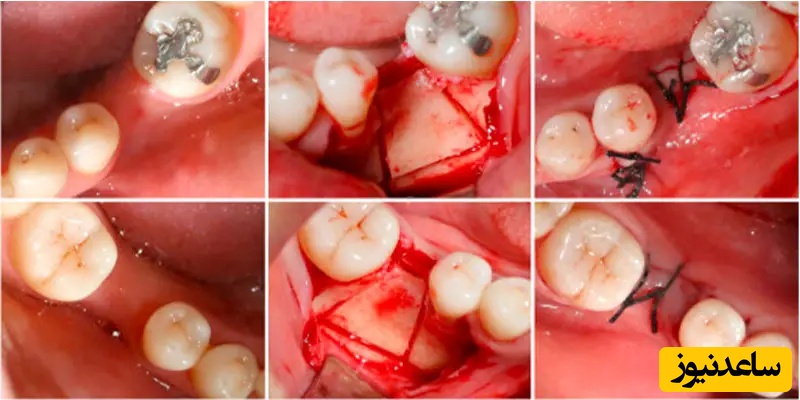

همان طور که گفتیم اگر در درون لثه استخوان تحلیل رفته باشد، برای انجام ایمپلنت به پیوند استخوان نیاز دارید. پیوند استخوان در ایمپلنت دندان یک عمل جراحی برای ترمیم یا بازسازی استخوان ها از طریق پیوند بافت استخوان است. در حقیقت پزشکان با پیوند بافت استخوان سالم، استخوان ها و بافت های پشتیبان ازدست رفته را از نو می سازند. پیوند استخوان برای ایمپلنت دندان با توجه به نوع پودر استخوان برای پیوند و همین طور میزان آسیب دیدگی استخوان فک و لثه به انواع مختلف تقسیم می شود که در ادامه بیشتر با آن ها آشنا خواهید شد.

این نوع عمل پیوند زمانی اتفاق می افتد که عمق تحلیل استخوانی تا 5 میلی متر از لبه استخوان تا سینوس بالای دندان رفته باشد. در این نوع عمل پیوند استخوان در ایمپلنت دندان که اصطلاحا لیفت سینوس گفته می شود به دلیل ضعف و شکنندگی بیش از حد مجاز استخوان فک و لثه بعد از قرار دادن مواد پیوند استخوان و بستن سینوس نیاز به گذشتن تقریبا 6 الی 10 ماه برای ترمیم استخوان فراهم آمدن شرایط کاشت ایمپلنت است.